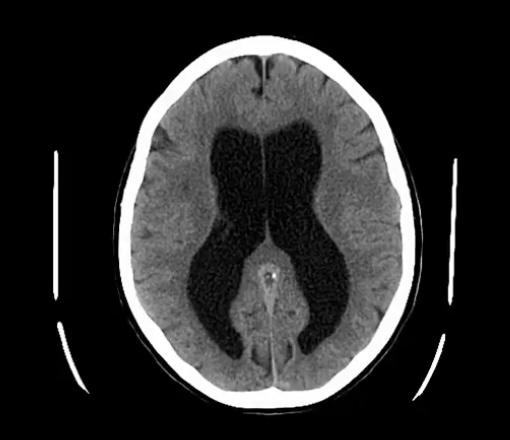

Hydrocephalus

-dilation of __, and accumulation of __

-2 main types…

COMMUNICATING HYDROCEPHALUS…

-named because there is communication between __

-due to decreased __ by the __, causing increased __

-a key sign of this is __

-a key sign on CT is __

-commonly occurs post-__, due to __

NON-CUMMUNICATING HYDROCEPHALUS…

-ventricles; CSF

-ventricles

-CSF absorption; arachnoid villi; ICP

-papilledema of eyes

-dilation of ALL ventricles

-meningitis; scarring